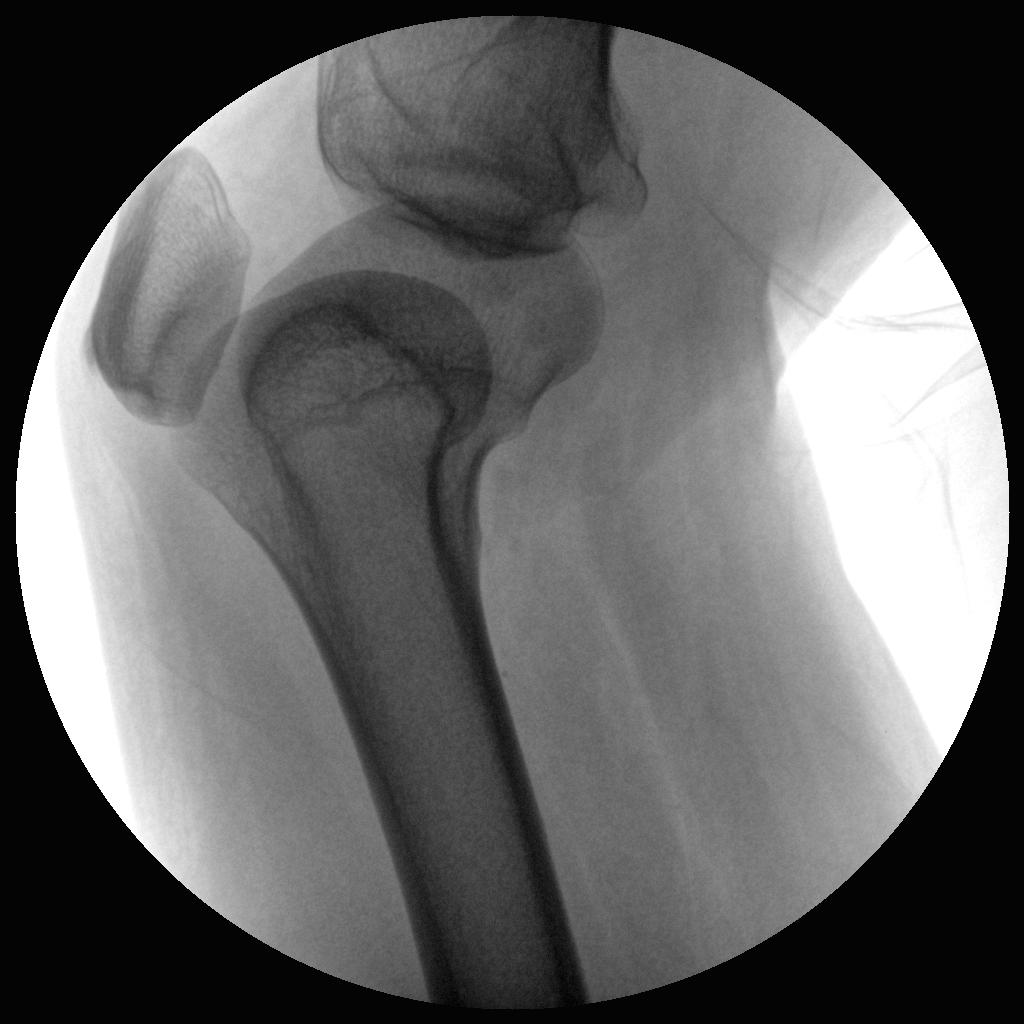

PLX112C 系列高频移动式手术X射线机

手术导航定位系统

●经典图文工作站,搭配双监双控,操作更自如●全数字化百万像素影像系统,图像清晰●独特的电动辅助支撑臂设计, 临床操作轻松自如●具备多种工作模式,满足更多临床需求●人体图形化触摸屏设计,操作方便快捷